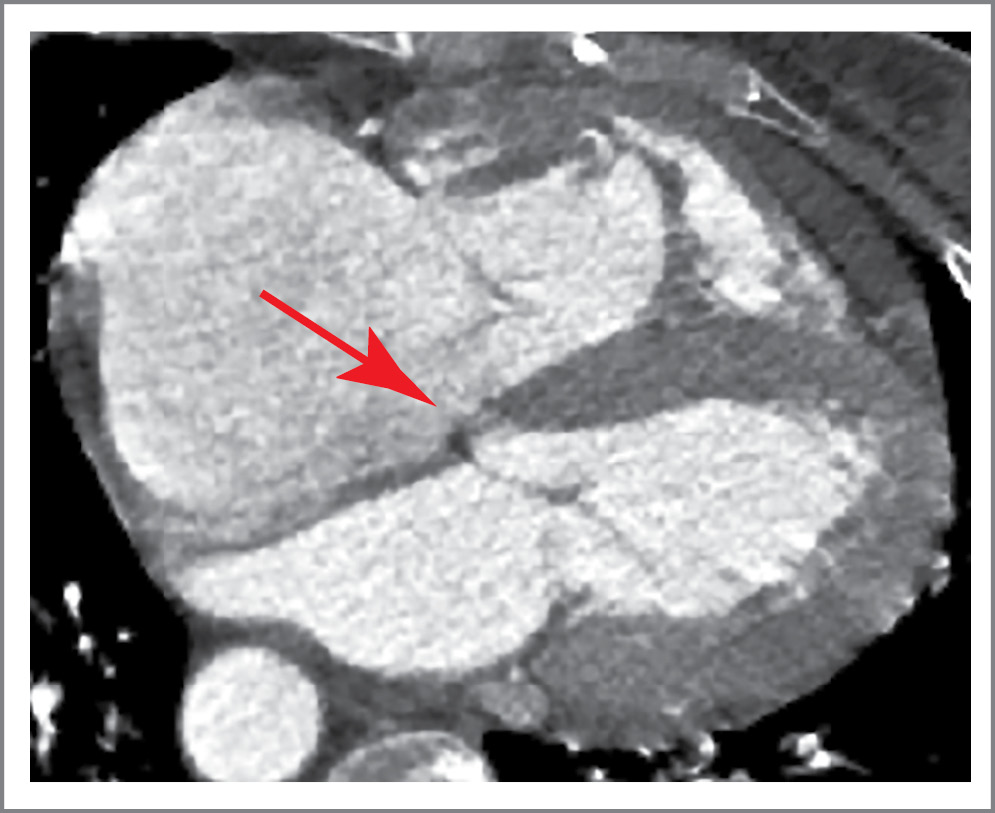

Мультиспиральная компьютерная томография аорты: кальциноз трехстворчатого АК 4-й степени, размер фиброзного кольца АК – 2,7×3,4×3,1×3,0 см. Определяется массивный кальцинат в проекции аортально-митрального контакта толщиной 0,6 см, протяженностью 2 см. Устье левой коронарной артерии расположено на 1,4 см, правой коронарной артерии – на 2 см выше фиброзного кольца АК. Диаметр аорты: на уровне синусов Вальсальвы – 3,7×3,8×3,9 см, восходящий отдел – 3,6 см, диаметр дуги – 2,4–2,5 см. В области мембранозной части межжелудочковой перегородки (МЖП) визуализируется дефект (рис. 2).

Рис. 3. Мультиспиральная компьютерная томография сердца с внутривенным контрастированием. Стрелкой указан дефект мембранозной части МЖП.

Fig. 3. Multispiral computed tomography of the heart with intravenous contrast. The arrow indicates the defect in the membranous part of interventricular septum.